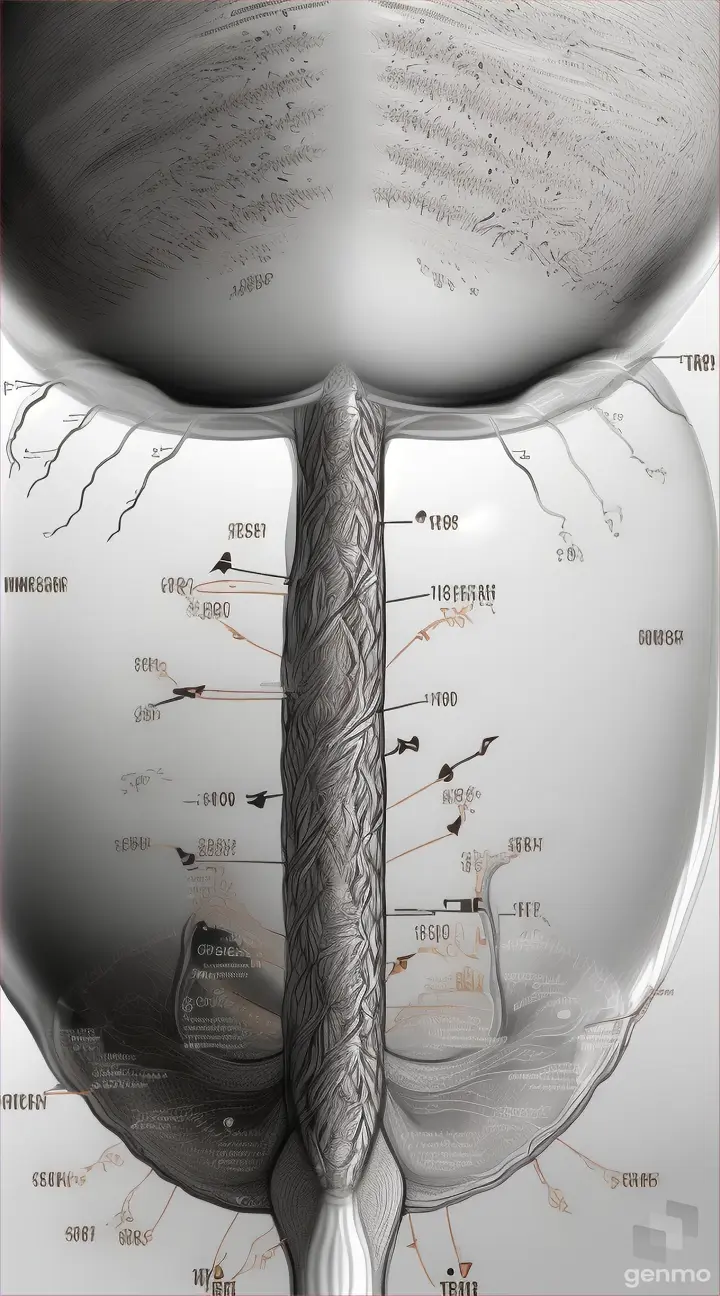

Prehistoric diet: Graphic representation of the types of food consumed by Tyrannosaurus rex, including meat, bones, and plants, based on scientific research.